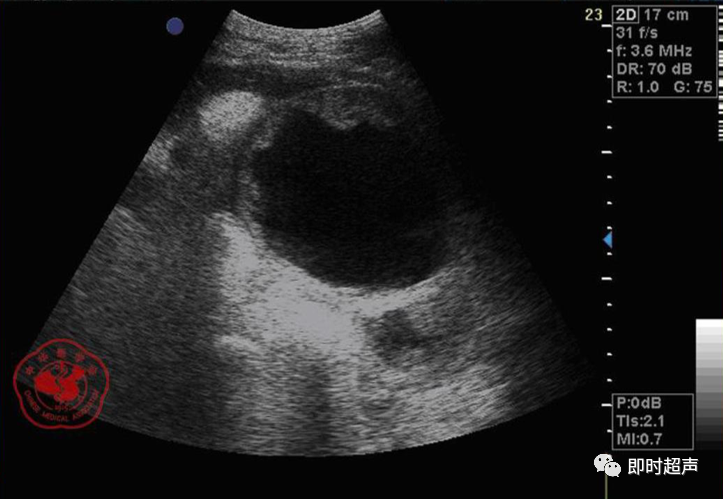

• GIST的发病机制与KIT信号通路的激活有关。• KIT是一种酪胺酸激酶跨膜受体蛋白,未经“装配”过的KIT蛋白是一种非活化的单体,参与细胞膜形成。几乎所有GIST都表达了KIT蛋白,而且大多突变的KIT基因保留了表达KIT蛋白的特性。c-kit内的突变主要见于恶性病例,特别是外显子11的点突变,还有外显子9、13和17,可以导致本质的或配体独立的c-kit激活,引发细胞的无序增殖和凋亡。这些具有功能的突变是GIST发病机理的关键,并且与肿瘤的恶性程度和预后较差相关。• GIST约75%发生于50岁以上老年人,中位年龄为58岁,无明显差异。• 可以发生在消化道从食道到肛门的任何部位,偶尔可原发于网膜、肠系膜和腹膜后,约50%发生在胃,25%发生在小肠,不足10%发生于食管、结肠及直肠。大体观察:肿块多境界清楚,类圆形,结节状,部分有假包膜。切面灰白、灰红,质韧,部分质嫩呈鱼肉状,伴有出血、坏死、囊性变。• 肿瘤组织主要由两种细胞组成,一种为长梭形细胞,细胞质丰富,嗜酸性,细胞核呈梭形或杆状;另一种为上皮样圆形或多角形细胞,细胞肥胖,胞质少。两种瘤细胞常呈束状、编织状或旋涡状排列。• 部分病例细胞异型明显,核分裂象增多,可见病理性核分裂象和瘤巨细胞。梭形细胞界不清楚,胞质丰富,淡染,轻度嗜伊红或略嗜碱,可有纤细、长梭形、短梭形或胖梭形、卵圆形,可见核仁。细胞核两端钝圆,部分病例胞质呈空泡状,位于核一端形成核端空泡胞,多呈交叉束状、旋涡状、席纹状及栅栏状排列。上皮样细胞胞浆丰富或透亮,多呈弥漫片状、束状或巢状排列。肿瘤间质可有出血、囊性变、坏死及黏液变,可见炎性细胞浸润。CD34抗原是一种115kd的糖基化蛋白,50%~80% GIST的CD34表达为阳性,CD34对鉴别GIST和典型的平滑肌瘤,神经鞘瘤还是非常有用的标记物,因后两者的CD34一般是阴性的。但CD34在诊断GIST上其特异性受到限制,一般情况下CD34多与CD117联合应用,方能提高GIST的诊断率。• 与肿瘤大小、发生部位、肿物与肠壁的关系以及肿瘤的良恶性有关。• 肿瘤较小者(直径小于2cm)常无症状,往往在体检和其它手术时无意中发现。• 肿瘤发生于胃肠道腔内时大多表现为呕吐、腹痛及消化道出血,而发生于胃肠道腔外的则主要表现为腹部包块。• 最常见的临床症状是中上腹部不适、腹部肿块及便血。• 对于临床发现的消化道(包括肠系膜、网膜、后腹膜)实体肿瘤,在排除其他常见肿瘤后,才考虑GIST。目前,诊断GIST有三条标准:③肿瘤组织具有梭形细胞和上皮样细胞两种基本细胞成分的病理学特征。这是诊断GIST金标准。CD117阳性者或CD117阴性而CD34阳性者,且伴平滑肌和神经双向分化或无分化者,可诊断为GISTs;以Desmin和SMA强阳性,而CD117阴性诊断为平滑肌肿瘤;以S-100阳性,CD117、Desmin、SMA均阴性诊断为神经鞘瘤。• GISTs的分型与组织学良恶性的关系:研究证实GISTs非单一分化的肿瘤,具有多向分化。• 当前GISTs的良性、交界性和恶性判断标准多参照Amin等提出的标准:②交界性:核分裂<5/50HPF,但肿瘤>5cm;• 另外研究显示,平滑肌型大多数为良性,少数为交界性和恶性,神经源型为恶性,双向分化亚型和未分化型为交界性和恶性,提示GISTs的分化型与其良恶性之间有一定关系。• 胃间质瘤早期多局部侵犯,后期出现肝转移和腹腔内种植,小肠间质瘤早期即可出现转移• 主要有超声扫描(检出率30%左右)、纤维内镜、超声内镜、CT、MRI、普通X• 线检查(胃肠钡餐造影、小肠插管气钡双重造影)、选择性血管造影检查等。• 不同部位的GIST,各种检查方法的敏感性不同。以CT检查为佳,尤其是螺旋CT,分辨率最高,可以三维重建,直接显示肿瘤大小、形态、密度、内部结构、边界,对邻近组织的侵犯也看得很清楚,同时还可观察其他部位的转移灶,有利于分期、鉴别与诊断。• MRI具有多轴成像及反映肿瘤内部成分的优点,尤其是动态扫描及各种新的扫描系列的出现更使其可以普及应用。• DSA检查对于GIST,特别是有消化道出血的患者更有价值。• 上述影像学检查表现并非特异性,与胃肠道平滑肌肿瘤、神经源性肿瘤鉴别困难。明确诊断要依赖病理免疫组化等手段。• 超声图像特征 肿物体积较小者(直径< 5. 0 cm )多为实性病变, 呈类圆形, 边界清晰, 内部回声多为较均匀的低回声。• 肿物体积较大者(直径> 5. 0 cm ) 多为混合性病变,呈不规则圆形或分叶状, 多数边界尚清晰, 以实性为主的病变内部为不均质中低回声伴不规则液性区及斑点状强回声; 以囊性为主的病变囊壁较厚,有分隔, 部分囊腔内可见点状、团状低回声。CDFI显示肿物实质回声内血流均较丰富。病例1:患者男, 62岁。自扪腹部包块2月余,包块增大20天就诊。查体:腹部平坦,无腹壁静脉曲张,无胃肠型及蠕动波,腹肌软,剑突下5cm处及左肋缘下可触及一质韧包块,大小约15*12cm,活动度差,边界尚清,包块深压痛,全腹无反跳痛。化验检查AFP:3.66(1.09-8.04)ng/ml,CEA:2.85(0-5)ng/ml。体格检查:一般情况良好,全腹软、平坦,腹部无压痛。超声检查:患者仰卧位时左上腹于胰尾前方可见一大小约6. 1 cm ×5. 8 cm ×5. 3 cm实性均质低回声,形态规则,包膜完整,边界清晰,活动度大;右侧卧时,肿块移至胰头右前方(图1) ;于其内探及丰富血流信号。体格检查:一般情况良好,腹丰满,上腹部有轻压痛,未扪及明显肿块。超声检查:患者仰卧位时左上腹于胰尾前方、脾门处可见一大小约10. 0 cm×8. 8 cm×7. 6 cm 实性低回声(图2) ,形态规则,包膜完整,边界清晰,肿块活动度大;右侧卧时,肿块移至左肝下间隙,回声尚均质;于其内探及较丰富血流信号(图3) 。图3 腹腔低回声肿块位于左肝下间隙,于低回声肿块内探及较丰富血流信号向壁外生长的胃肠道间质瘤, st为胃腔,箭头所指为胃壁, T为向外生的肿瘤• 胃间质瘤的定位准确率要高于十二指肠及小肠间质瘤,这主要是因为胃的解剖位置相对固定,且通过饮水使胃腔充盈,可清晰的显示胃壁的各层结构及肿块与胃壁的关系。肿块多表现为粘膜下、肌层或浆膜下低至中等回声团块,可向腔内、腔外或腔内外生长。但当肿瘤较大或浸润周围脏器时,超声定位仍有困难, 因此,超声如发现上腹部肿块且怀疑来源于胃者,应尽可能嘱其饮水充盈胃腔,并多角度、多切面观察肿块与周围脏器的关系,以提高定位的准确性。• 十二指肠间质瘤的定位亦较准确,但降部的外生性肿块常与胰头粘连而误诊为胰腺肿瘤回声均匀且位置较深的间质瘤亦可能误为胰头周围淋巴结。• 空、回肠间质瘤常因肿块较大,多发,位置不固定而难以定位,往往误诊为腹、盆腔或腹膜后肿瘤,超声检查如发现肿块局部肠壁增厚,肿块与肠道随呼吸同步运动时可作出定位诊断。• GIST的声像图表现有助于其良、恶性的鉴别:良性肿瘤多体积较小,圆形或椭圆形,回声均匀,边界清晰。恶性肿瘤多较大,呈不规则分叶状,回声不均匀,内部易出血、坏死、囊变。• 肿瘤长径与肿瘤内部是否出现无回声区在良、恶性病变之间的差异有统计学意义,是判断良恶性的有效征象。• 如以肿瘤长径>5cm为诊断恶性标准,其敏感性、特异性及准确性均较理想。超声可为临床提供胃肠道间质瘤的部位、大小、边界、回声等较多有用信息,一部分病例可作出定位、定性诊断,并可在术后或复发患者药物治疗期间对其进行动态观察;CDFI方便快捷、无需造影剂即可对间质瘤周边及内部血流进行观察,可为临床医师提供肿瘤血供情况。但未发现腹腔或肝脏转移时,超声判断胃肠道间质瘤性质有一定难度。• 目前临床上对GISTs的治疗效果并不十分满意。治疗仍以手术为主,对无法手术切除或已有转移的GISTs患者进行甲磺酸伊马替尼化疗。• 手术方式取决于肿瘤大小、部位和术中冰冻切片结果等。• 发生在胃的间质瘤,可首选胃大部切除术;发生在十二指肠的间质瘤可行保留胰头的十二指肠切除术或胰十二指肠切除术;发生在小肠的间质瘤可行肿瘤肠段切除术;发生于结肠的间质瘤可行左半或右半结肠切除术;发生于直肠的间质瘤可行肿瘤局部切除术。一般情况下无需淋巴结清扫。• 术后随访监测,复发者单个病灶可考虑手术切除;多发或转移特征者应试行甲磺酸伊马替尼化疗,并监测肿瘤大小及数目的改变。• 随着分子靶点药物进入肿瘤临床,一种小分子化合物———酪胺酸激酶受体抑制剂,美国称为Gleevec,欧洲叫做Glivec(格列卫),在治疗GIST和慢性粒细胞白血病方面有其独特的作用。已知细胞膜表面上皮生长因子受体酪胺酸激酶抑制剂大致分为两大类:一类是小分子化合物;另一类是特异性抗体。利用抑制酪胺酸激酶的活性,对处于增殖期状态的病变具有治疗的作用。Glivec在体外、体内和细胞水平都可强烈抑制酪胺酸激酶的活性,是干细胞因子(SDCF)受体KIT的强抑制剂。• Glivec推荐用量为400mg(4片),每日一次, 3个月为一疗程。如服3个月后无效可加至600mg/d~800mg/d(6~8片)[18];若仍无效果不再增量应停止治疗。• Glivec治疗进展转移的GIST总有效率为50%左右,比传统化疗有效率高十倍以上;肿瘤生长控制率达80%以上,起效最快在服药后24h之内,使症状改善如疼痛缓解;平均起效时间为13周(约3个月)。患者体力状况改善是又一突出效果。2/3患者治疗后无症状可如健康人生活工作。• Brainard等研究发现间质瘤预后差的前两位因素为肿瘤大小和核分裂象,故对于间质瘤直径>5cm和核分裂象>5/50HPF的患者应给予口服Glivec。最近,Liu报道口服Glivec治疗可使85%患者的病情得到控制。